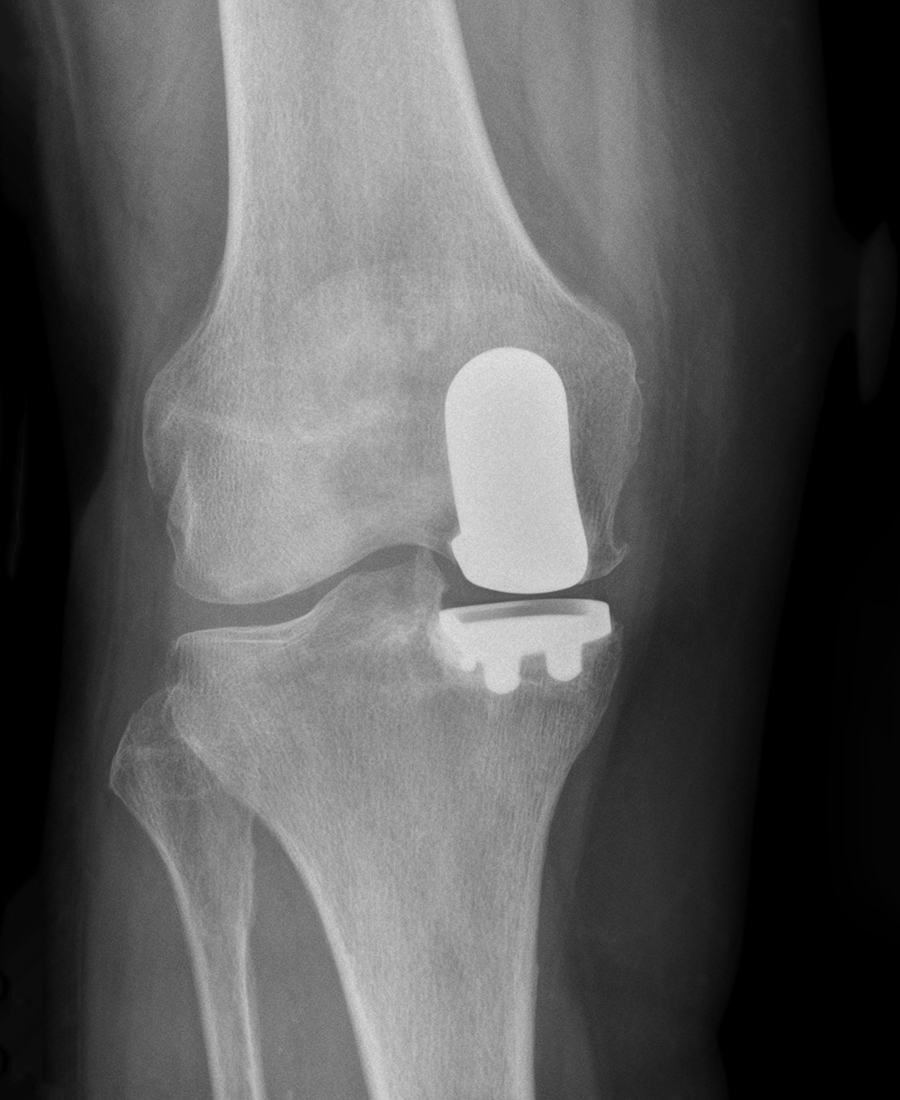

Unicondyläre mediale Schlittenendoprothese

mediale Schlitten-Endoprothese, Mako-Robotik-Implantation

- OP-Tag: Implantation der Prothese nach CAD-Planung, Röntgenkontrolle nach Leitlinie noch im OP, um den Implantsitz zu prüfen

- Röntgenkontrolle vor Entlassung (Beinachsenaufnahme, Bemessung der Biomechanik)

Was ist der Unterschied zwischen Teil- und Vollprothese?

- Teilprothese (Schlittenprothese/unikondyläre Prothese): Ersetzt nur den geschädigten Teil des Kniegelenks (medial oder lateral). Geeignet bei isoliertem Kompartmentschaden mit intakten Bändern.